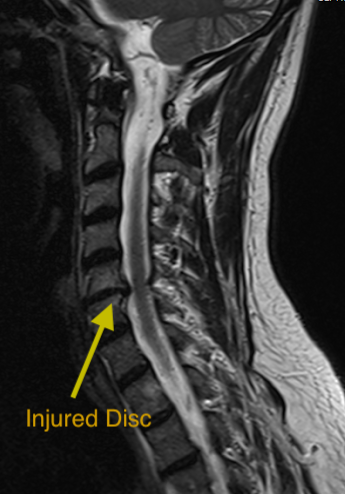

Injured Disc In Neck

After anesthesia is given, a ~2.5 inch incision is made on the front of the neck. The windpipe and esophagus is moved over the side, the injured disc is removed, and the nerves and spinal cord are carefully relieved of the damaging pressure.